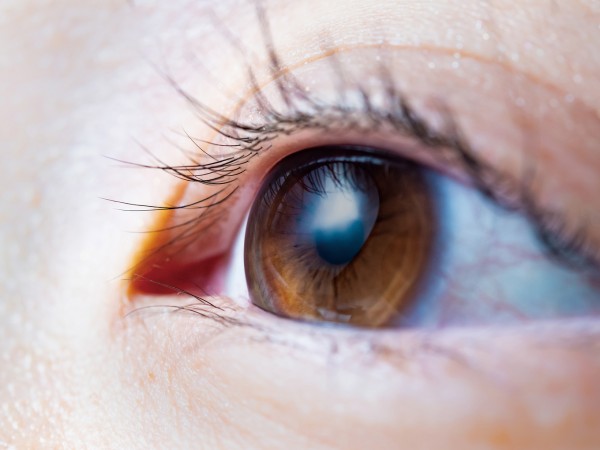

2024年12月21日ICL治療の「感動的な視界」は本当か。

2024年12月21日ICL治療の「感動的な視界」は本当か。

いまや私たちの快適な生活の基盤となったデジタルツール。だが、身の回りをぐるりと見渡してみると、目の前にはPC用のマルチディスプレイ、脇には…

記事をもっと見る 2021年9月17日専門医であり経験者。広島の認定医に訊く「ICL治療」の魅力。

2021年9月17日専門医であり経験者。広島の認定医に訊く「ICL治療」の魅力。

視力矯正の新たな選択肢「ICL治療」で取り戻す、クリアで快適な視界。 新型コロナウイルス感染症のワクチン接種が進んでいるとは言え、しばらく…